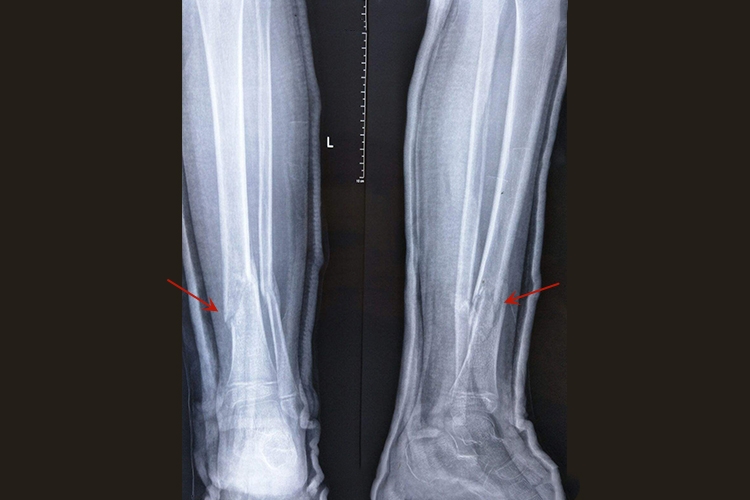

胫骨骨折迟缓愈合:胫骨骨折经治疗后,已超过同类骨折正常愈合的最长期限,骨折处局部仍有肿胀、压痛,纵轴叩击痛,异常活动,功能障碍。X线片显示骨痂生长缓慢而未连接,但骨折断端无硬化现象,骨髓腔仍通。

胫骨骨折不愈合:是指胫骨骨折愈合功能停止,骨折端已形成假关节。X线片显示胫骨骨折端互相分离,间隙增大,骨端硬化或萎缩疏松、髓腔封闭,用一般的固定方法无法使之连接。